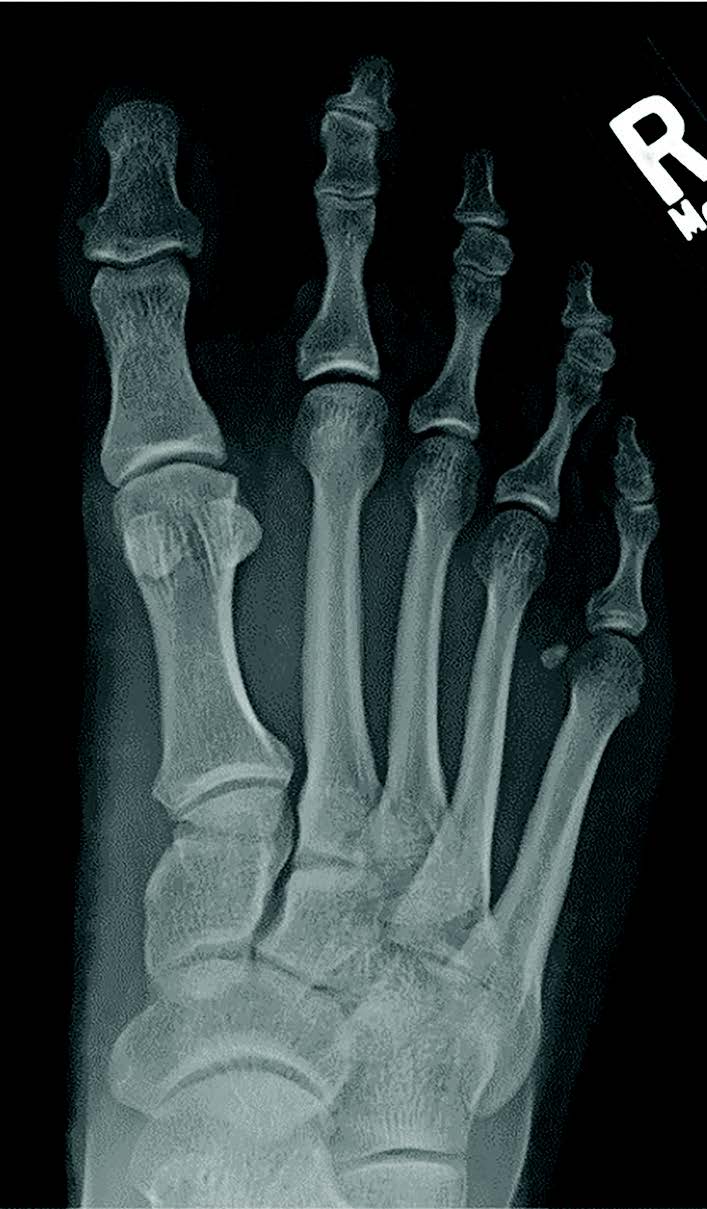

The literature traditionally presents idiopathic hallux varus as a rare clinical entity.1,2 Unfortunately, there is currently a paucity of literature related to idiopathic hallux varus, with iatrogenic hallux varus appearing more frequently in publications. Over 30 years of tracking clinical and radiographic cases, I have amassed encounters of over 700 cases of idiopathic hallux varus. We have catalogued 153 cases within our radiographic database at Ft. Leonard Wood in the last 5 years. Many would think hallux varus to be a severe deformity (see left two images below), but in reality, most of what we all tend to see is less extreme (see right image below).

Secondary hallux varus typically relates to great toe polydactyly, a delta phalanx, longitudinal epiphyseal bracket syndrome, and metatarsus adductus (see images above).6 Historically, there is also mention of a tertiary type, associated with severe skeletal abnormalities such as diastrophic dwarfism.7 Unfortunately, the literature is sparse regarding pediatric hallux varus, but within my pediatric population we see kids developing hallux varus who do not have a history of metadductus or even a spastic abductor (see images below).

Within our database, to date, we have not seen a negative intermetatarsal angle in any idiopathic hallux varus case. We routinely see normal intermetatarsal angles and often see some greater than 10 degrees. We routinely see normal sesamoid positions. In our experience, the deformity is almost always a negative PASA deformity. For iatrogenic, it seems like everyone focuses on the sesamoids, but there can be multiple permutations of sesamoid shape, position, or even lack of sesamoids. I then wondered if metatarsal length played a role, but my archives show multiple cases with short and long first metatarsals (see images below). All have the same etiology, incongruent first MTPJ, and negative PASA.